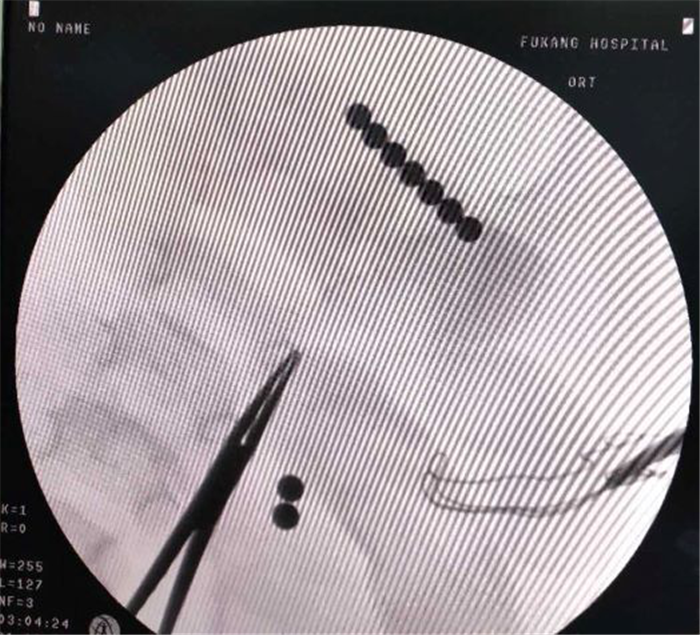

(图4)肠道内的“磁力珠”

普外科陈主任主刀,闫孟主治医师一助,王进坤主治医师二助,术中发现因直径5mm彩色“磁力珠”长时间在肠道内,已造成肠内5处穿孔,其中2粒在空肠,7粒在升结肠(图4),空肠3处穿孔,升结肠2处穿孔,肠系膜广泛淋巴结肿大,幸运的是穿孔直径均在2mm以下,患儿纳差,大便干结,无食物残渣、粪便及较多肠液进入腹腔,腹腔仅约100ml淡黄色清亮渗液,没有明显的腹腔污染,为其行“肠腔异物取出术+肠穿孔修补术+腹腔冲洗引流术”,成功取出肠腔内9枚彩色圆形金属异物(图1)。